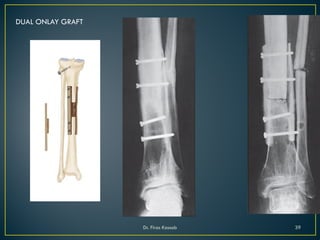

DUAL ONLAY GRAFT

• Two cortical onlay grafts are placed opposite each other on the

host bone across the nonunion and are fixed with the same set

of screws

• They grip the fragments like a vise

• Uses-

to fix nonunited short osteoporotic

fracture near a joint

ADVANTAGE

• Mechanichal fixation is better than fixation by a single onlay

bone graft

• two grafts add strength and stability

• Grafts form a trough into which cancellous bone may be

packed

• during healing the dual graft prevent contracting fibrous

tissue from compromising transplanted cancellous bone